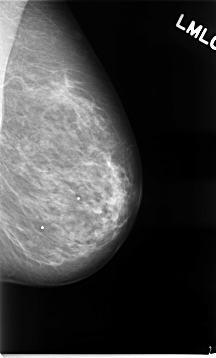

C_0041_1.LEFT_MLO

LEFT_MLO LINES 4648 PIXELS_PER_LINE 2808 BITS_PER_PIXEL 12 RESOLUTION 50 NON_OVERLAY